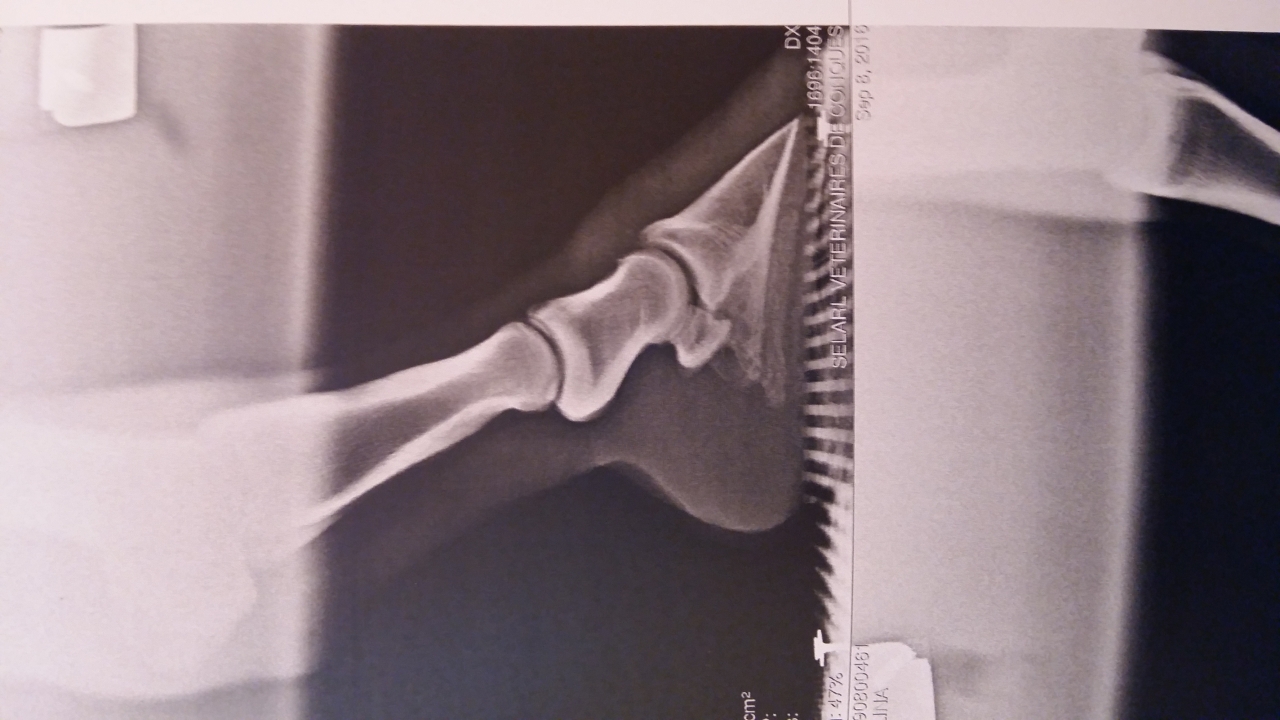

| Dire merci | Bonsoir Bon je suis un peu perdue. On a fait des radios sur ma jument de 18 ans il y a un mois à l'issue desquelles le veto m'a annoncé clairement une sole très très fine sur les 2 antérieurs avec AD légèrement plus encastelé. Il m'a conseillé ferrage avec plaque en cuir ou hipposandales lors des sorties. MAIS clairement la jument a un autre problème qui fait que je vais maintenant arrêter les sorties longues et le travail en carrière (voir le post "bilan clinique avis" . Je ne ferai plus que de courtes balades au pas pour la forme et le moral. Seulement je l'observais au pré l'autre jour ..... elle en bave clairement .... elle ne boite pas comme sur du dur mais elle ne fait pas de folies non plus. Quand j'ai appelé les chevaux ils sont tous arrivés au galop et elle elle a tenté un petit trot mais finalement elle n'a fait que quelques foulées avant de repasser au pas. Certains m'ont dit -pieds nus + hipposandales sur le dur -pieds nus + hipposandales H24 Mais j'ai lu que c'était pas génial de laisser un pied tout le temps enfermé dedans ?? -ferrure légère orthopédique Oui c'est quoi ? -ferrure classique +plaque comme dit le veto Pour rappel voici les radios : ![]() ![]() Autre rappel:ça fait 5 ans que la jument est pieds nus. Merci !! |

| Dire merci | Vu les radios, c'est de la "maltraitance" de la laisser sans fer. Elle doit souffrir au quotidien. Alors une paire de fer au moins pour l'éloigner du sol sera une bonne chose. Après a voir si tu veux investir dans de l'orthopédie ... mais au moins des fers avec un bon roll.... |

| Dire merci | Enfin là on est au delà de la sole fine (comme pour ma jument), c'est PATHOLOGIQUEMENT fin. C'est pour ça que je n'ai pas foncé tête baissée dans "on ferre". Il faut absolument soulager la jument (c'est l'erreur que j'ai fait, en pensant que le temps ferait bien les choses... nawak), mais il faut trouver un moyen de faire pousser la sole. Même ferrée, avec ses quelques mm de sole, le moindre cailloux lui fait mal. Et suspendre P3 avec le fer sans sole en dessous n'est pas plus beaucoup plus confortable ou à court terme... Donc vois : - éventuelles carences - Parage à plat trop invasif - Manque de vascularisation (ça passe par le mouvement) - juste la vieillerie : booster avec de la biotine? - pour soulager : PHW plutôt que les chaussures. Je les ai posé moi même après une première pose, ça tient plusieurs semaines sans soucis. Le temps va être en ta faveur, les terrains vont mollir. Après des semaines de sensibilité, ma jument prend difficilement le trot et le galop (elle n'a pas encore confiance je pense) sauf si sol magique genre sable. Je lui laisse le temps. Elle marche d'un très bon pas, c'est déjà une victoire. |